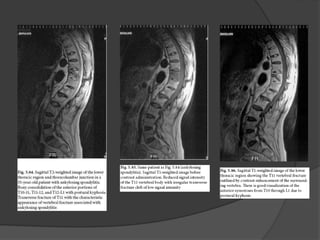

Exames de Imagem

 RNM.

RM